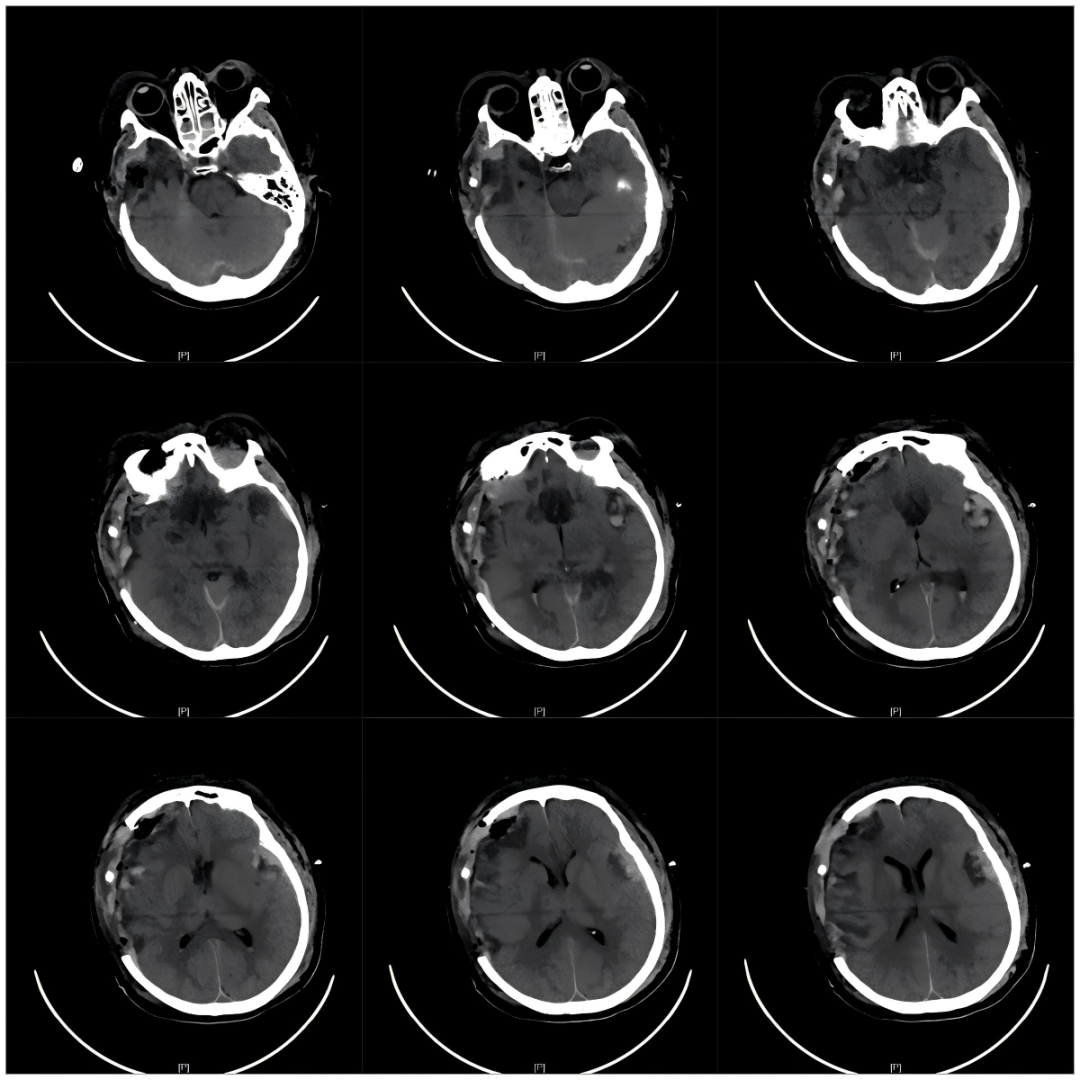

▲急诊术前CT影像

68岁的张女士(化名)

因严重车祸导致颅内出血及全身多发伤

急诊行开颅血肿清除术后

生命体征虽稳定

却陷入微小意识状态-(MCS-)

术后3个月

其意识水平仍停滞GCS:5T(M3VTE2)

仅能通过疼痛刺激短暂睁眼

但无法言语交流,生活完全依赖护理